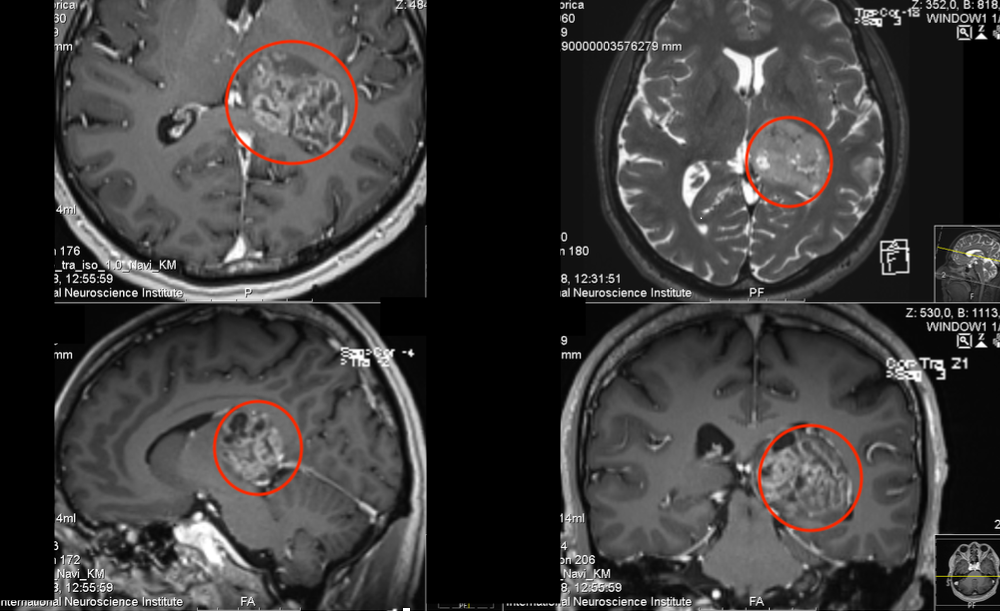

作为钢琴演奏家、钢琴老师的Z女士,大约4个月前发现出右手弹奏不灵活,细致活动限制,头部右侧和右脚麻木感,也偶有视力模糊、有雾感,起初本以为是太劳累所致,却不见好转,当地医院就诊,在当地医院发现丘脑内较大占位,考虑胶质瘤可能。Z女士而后辗转多处,得知德国Helmut Bertalanffy(巴特朗菲,国内病人尊称“巴教授”)在这领域的丰富成功经验,成功联系并进行了二意见咨询,得到可以手术全切的回复后,一家人带她前往巴特朗菲教授所在的德国汉诺威INI国际神经学研究所进行手术治疗。

在5-ALA荧光、术中神经导航和术中MRI辅助手术,通过左侧顶枕枕骨开颅术和显微外科肿瘤全切手术,手术顺利,无手术并发症。患者术后当天即拔出气管插管,无任何问题,转入重症监护室进行观察1天。术后当天与术前相比,右手和手臂仍有轻微的偏瘫和轻度运动无力,无言语功能障碍。术后2天,检查术后CT正常,无血肿和明显脑水肿等,该患者的临床状况迅速好转,并迁出ICU。术后3天即在物理治疗下增加康复锻炼,下地锻炼,术后5天即可自行站立行走。在INI住院期间,手细致功能障碍、言语和感觉偏瘫均得到好转。右手的细致运动技能也比手术后开始时明显好转。